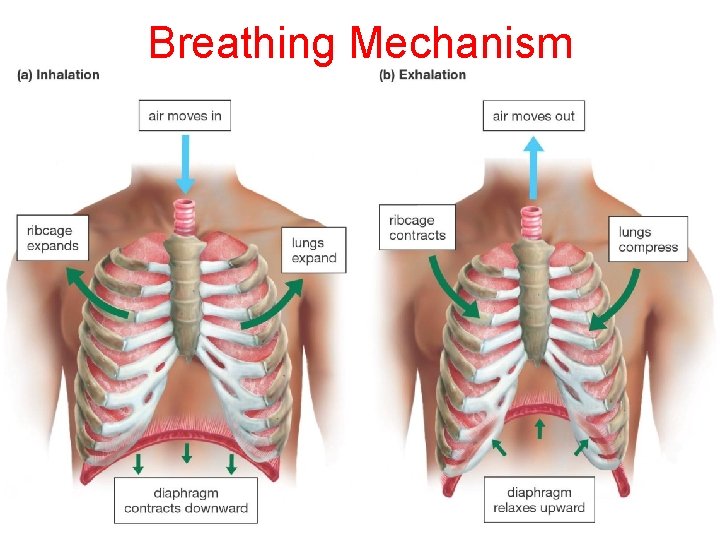

Breathing Mechanism

Breathing Muscle Demonstration 1) Close Mouth & Hold Nose 2) Then Try To Inhale 3) Then Open Mouth 4) Close Mouth and Open the Nose What is different?